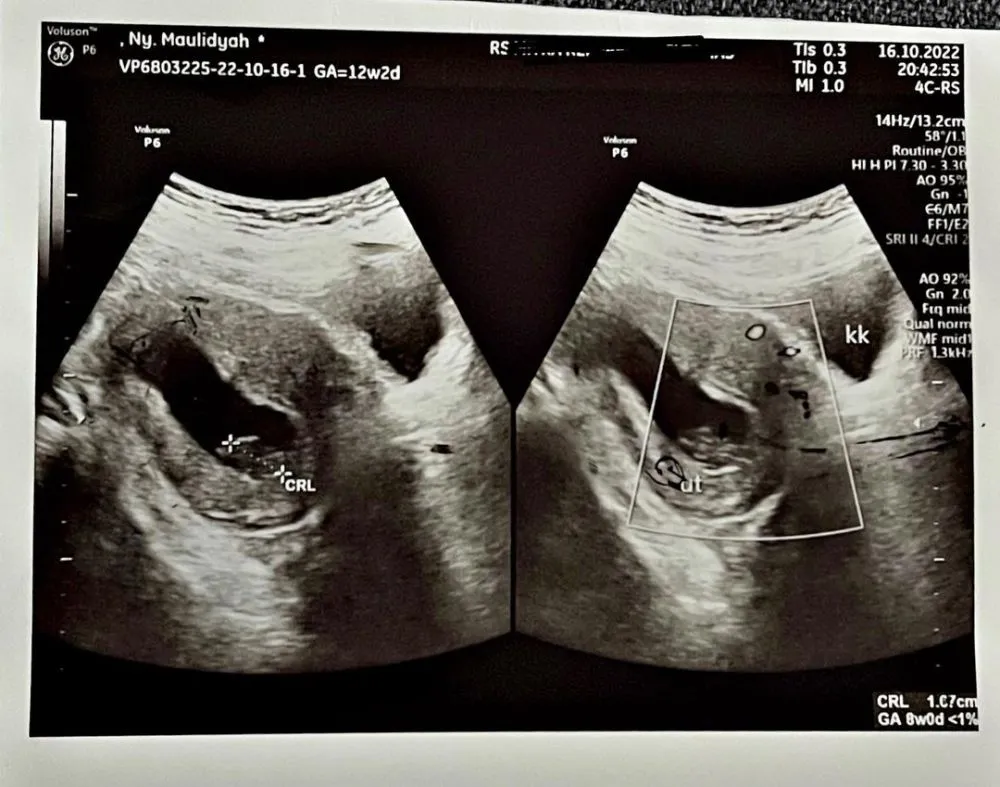

Melansir dari Instagram @viavallen, Rabu (26/10), dokter mengatakan janin berhenti berkembang di usia 8 minggu, yang seharusnya saat itu janin sudah di usia 12 minggu. Janin yang ada di perut Via sudah tak berkembang selama 1 bulan.

via vallen keguguran © Instagram

foto: Instagram/@viavallen